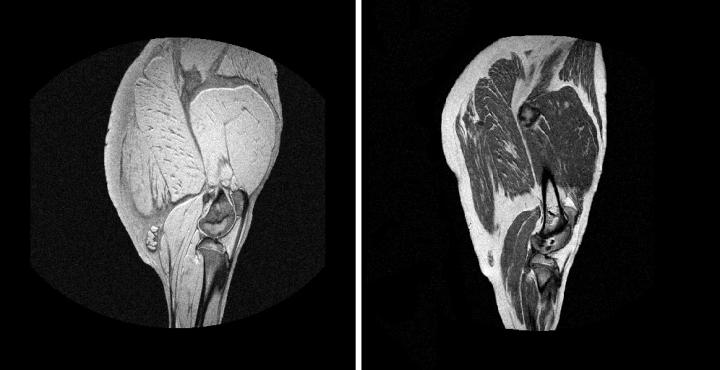

Researchers from the University of Extremadura (Spain) have developed a methodology that allows us to know the properties of hams and whole loins using magnetic resonance imaging, the same non-invasive technique used in medicine. The method has already been made available to the meat industry.

Magnetic resonance imaging (MRI) is commonly used in medicine to look at organs and structures inside the human body. Now researchers from IProCar - the Meat and Meat Products Institute - of the University of Extremadura have applied this same technology, based on the non-invasive use of magnets and radio waves, for something very different: to know the characteristics of Iberian hams and loins without need to destroy them.

Once the images are taken, the scientists analyze them with computer vision algorithms and extract numerical values on which, in turn, they apply statistical methods. In this way, the quality characteristics of meat products can be predicted.

"The technique allows knowing parameters such as the amount of fat, moisture, color and some sensory attributes of the product; and in the case of ham, also monitoring the salt diffusion during the different stages of the maturation process," explains Trinidad Pérez Palacios, a member of IProCar.

The studies carried out with this methodology have been published in several scientific journals, such as the Journal of Food Engineering , where this year Extremadura researchers have presented a paper focused on the application of texture algorithms to three-dimensional MRI images to predict the quality of the loins.